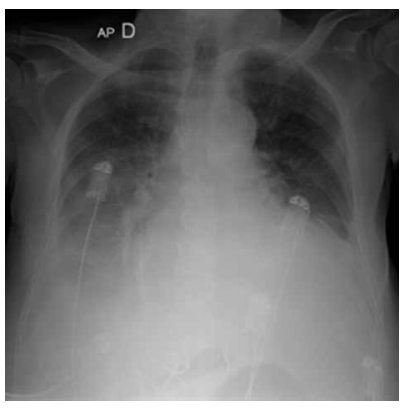

Homem, 76 anos, hipertenso e portador de miocardiopatia isquêmica, queixa-se de mal-estar, dispneia em repouso, dispneia paroxística noturna e, na última semana, ortopneia. Medicamentos em uso: captopril 25 mg; a cada 8 horas; furosemida 40 mg; espironolactona 50 mg; aspirina 100 mg e sinvastatina 20 mg. Exame físico: paciente lúcido e orientado no tempo e no espaço, presença de edema em membros inferiores 4+/4, extremidades frias, perfusão lentificada, pressão arterial = 90 x 50 mmHg, SpO2 = 89%, ausculta cardíaca com terceira bulha e ausculta pulmonar com estertores crepitantes nos dois terços inferiores de ambos os pulmões. Realizada radiografia de tórax, que está ilustrada a seguir.

O tratamento correto deverá, obrigatoriamente, incluir